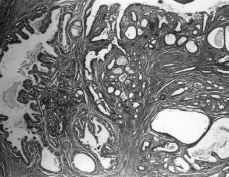

Macroscópicamente, cada una de las mamas era de configuración ovoide, de consistencia semiblanda y multinodular a la palpación. La mama derecha pesó 487 g y midió 16 x 12,5 x 5,2 cm en sus dimensiones máximas. La mama izquierda, de mayor volumen, pesó 848 g y midió 20 x 16 x 6,8 cm. La apariencia macroscópica era similar en uno y otro lado. La superficie externa era lobulada y sin restos aparentes de glándula normal. Al corte, la superficie era multinodular, alternando con cavidades de configuración variable conteniendo líquido turbio de color pardo rojizo con material mucinoso de color pardo grisáceo claro en ocasiones con tinte amarillento (Fig. 2). Los nódulos de forma esferoidal u ovoide median entre 0,3 y 4,5 cm y algunos aparecían como unidades confluentes. Después de fijación formólica se destacaron cavidades limitadas por una pared de grosor variable, repletas de un tejido con inequívoca apariencia papilar (Fig. 3). El tejido internodular era más bien escaso, de aspecto uniforme, de color gris rosado claro o blanquecino, brillante y de consistencia semiblanda. No se apreció ni necrosis, ni hemorragia, ni calcificaciones. Microscópicamente, los cambios estructurales eran similares en ambos lados. Predominaban los conductos galactóforos con grados variables de dilatación, desde la típica apariencia en «queso suizo» hasta macroquistes con más de 2 cm de diámetro (Fig. 4). La luz se encontraba ocupada por multitud de frondas papilares con ejes conjuntivos revestidos por una capa de células epiteliales cúbicas, ovoides o cilíndricas con escasa anisocariosis y mitosis aisladas. También se encontraron conductos con incremento del número de las capas de su revestimiento epitelial dando lugar a la formación de luces secundarias de configuración irregular y de distribución predominantemente periférica. No existían atipias citológicas. En algunos conductos dilatados se apreció metaplasia apocrina con pequeñas proyecciones papilares sin eje conjuntivo. Se visualizaron igualmente campos en los cuales llamó la atención una proliferación bifásica con rasgos similares a los que se aprecian en un fibroadenoma juvenil (Fig. 5). En ninguno de los múltiples planos de sección apreciamos glándula mamaria residual y el estroma entre las estructuras previamente descritas consistió en tejido conjuntivo con cantidades variables de colágeno en la matriz extracelular. El diagnóstico anatomopatológico definitivo fue de papilomatosis juvenil difusa y bilateral.

Figura 5. Proliferación bifásica de arquitectura papilar (hematoxilina-eosina x 100).